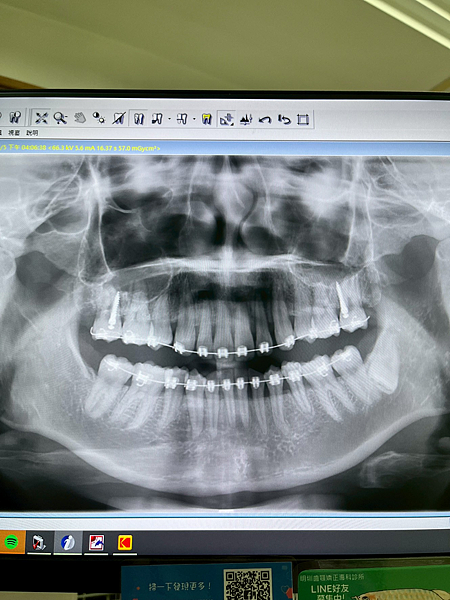

其實我的牙齒下排少了兩顆牙,所以是有空隙的,上排牙齒過於壅擠所以矯正必須拔兩顆牙,而且上排門牙上還有個多生牙,必須先拔除,不然矯正的時候調整可能撞到,導致原本的門牙牙根受損

2022/01/25第一次去診所做評估掛號費100元,評估費用式4000元(包含拍照、X光片、掃描牙齒)

照X光發現我的上顎有個多生牙,我必須先轉診到別的地方拔除,以免矯正的時候傷到原本牙齒的牙根